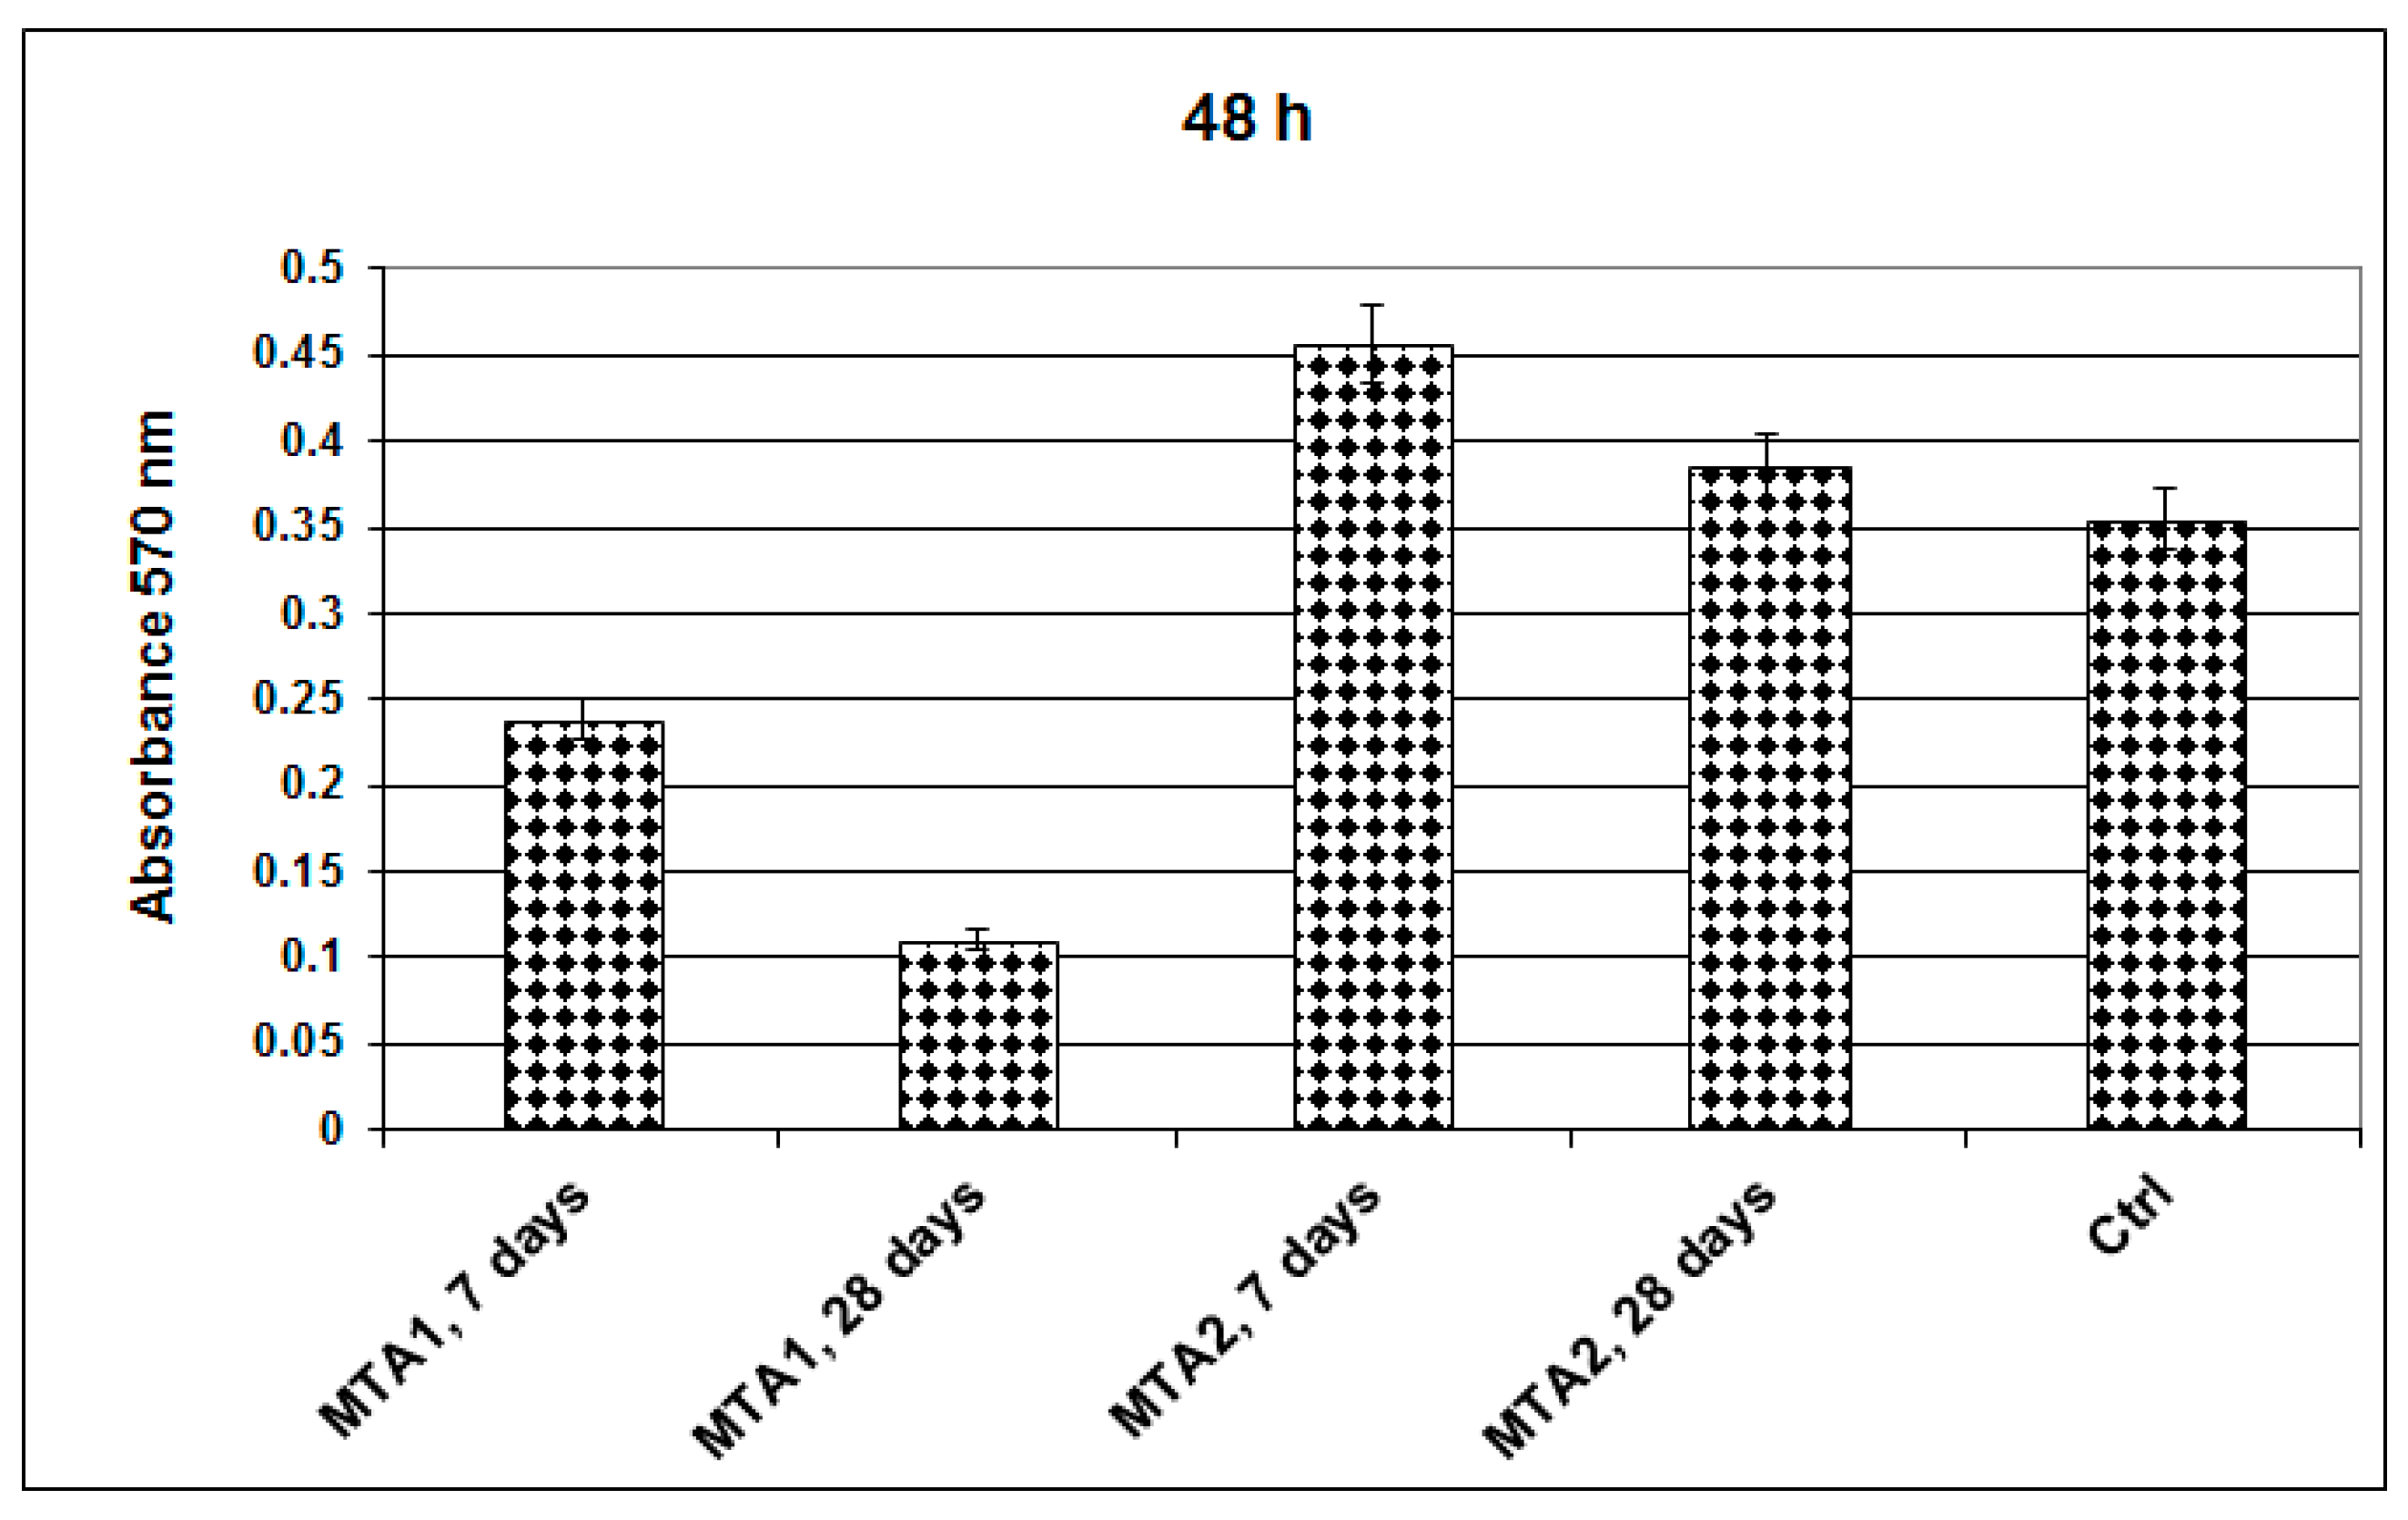

- MTT assay